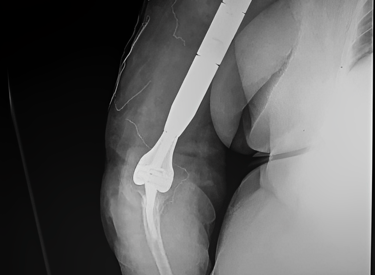

Fabricación 3D

Impresión 3D en titanio trabecular con tecnología láser MBPF, generando una óptima osteointegración. Entrega de biomodelos y guías de corte para una perfecta colocación en quirófano